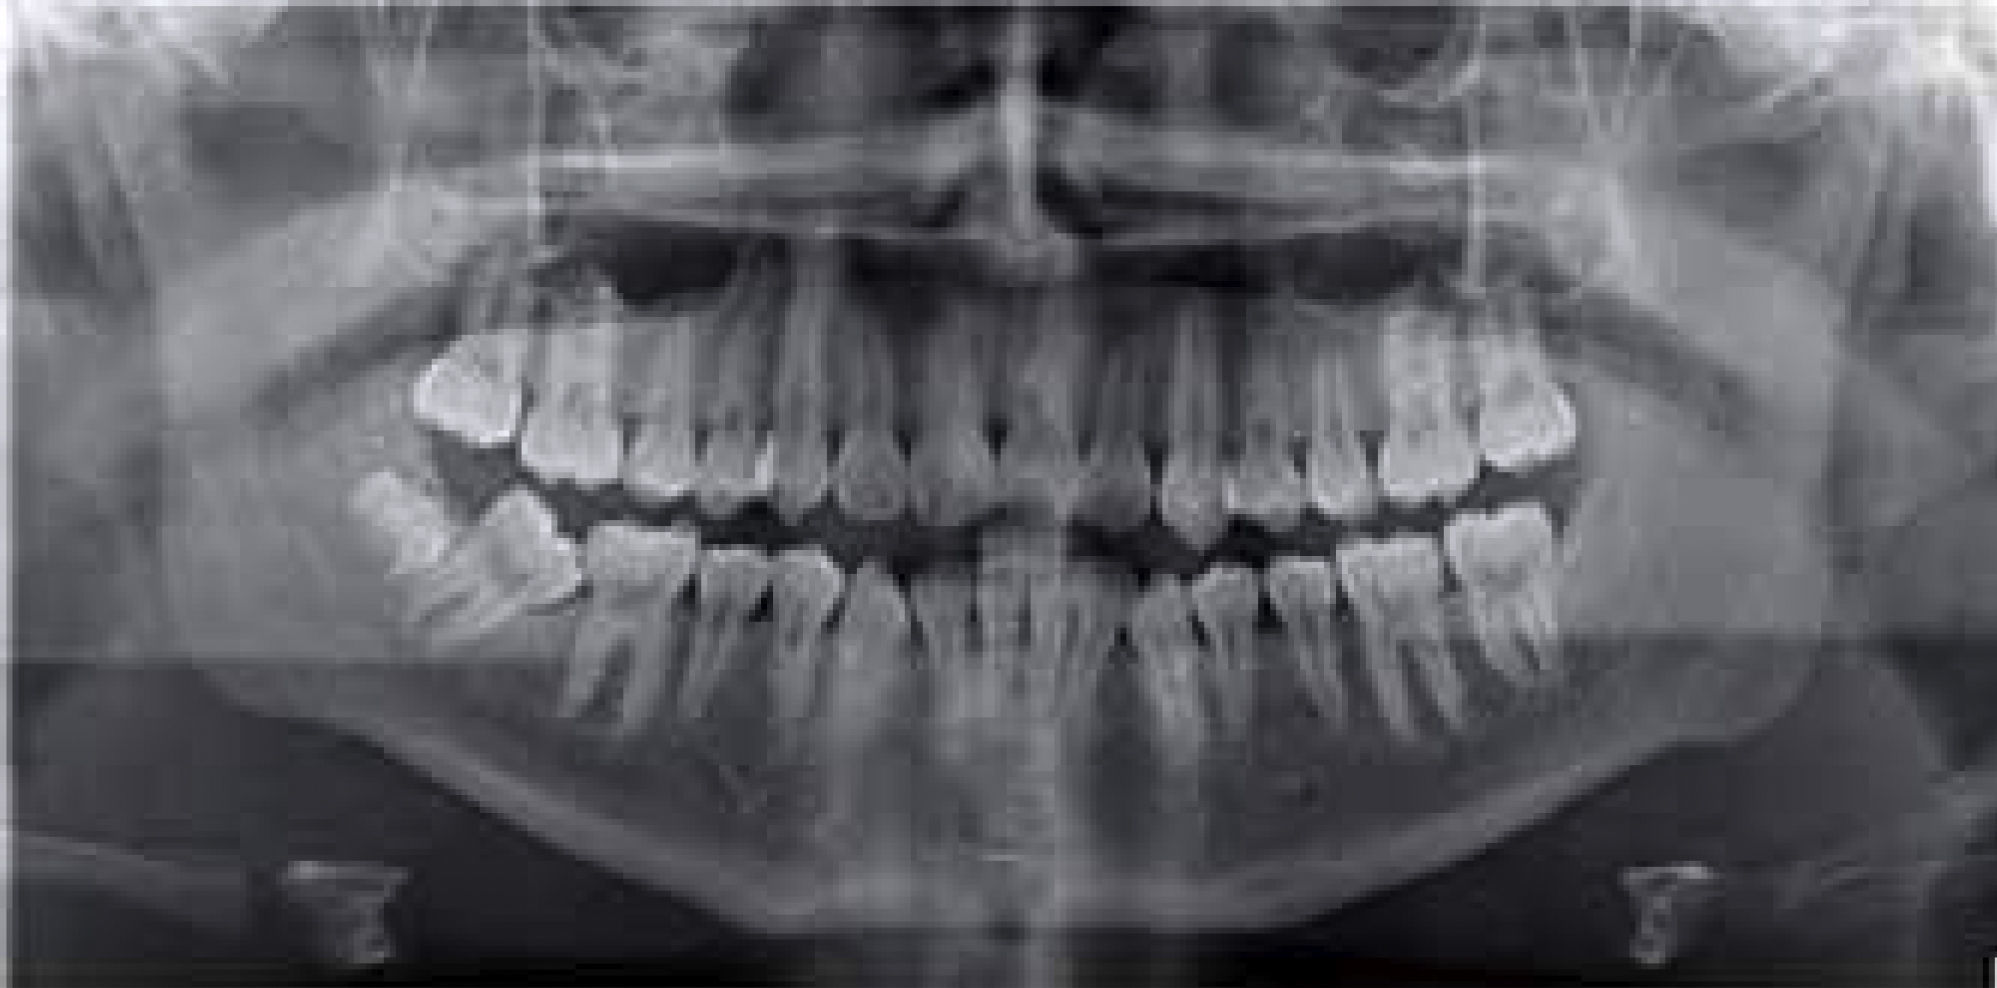

Symmetric maxillary sinuses were observed in the radiographic analysis, and loss of interproximal alveolar crests, short roots of the dental organs #31, 32, 41 and 42, absence of the third molars, only dental organ #48 and mesial inclination of the lower right second molar (Figure 3).